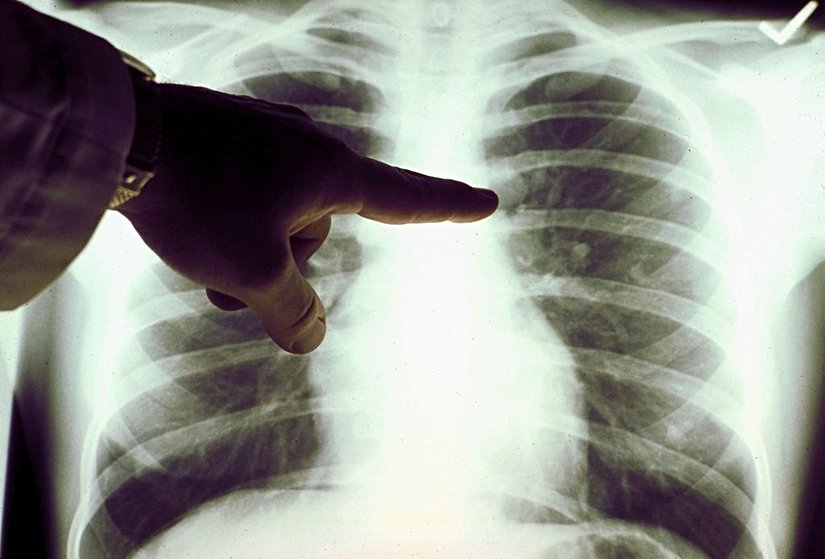

Bir doktor, sadece röntgen görüntülerine bakarak hastanın siyahi mi, Asyalı mı, yoksa beyaz mı olduğunu ayırt edemez. Massachusetts Teknoloji Enstitüsü ve Harvard Tıp Okulu'ndaki araştırmacıları da içeren uluslararası bir ekibin The Lancet Digital Health tıp dergisinde yayınladığı şaşırtıcı bir makaleye göre bir bilgisayar bunu yapabiliyor olabilir![2]

Çalışma, X-ışınlarını ve CT taramalarını okumak için eğitilmiş bir yapay zeka programının, bir kişinin ırkını %90 doğrulukla tahmin edebileceğini buldu. Ancak çalışmayı yürüten bilim insanları, bilgisayarın bunu nasıl çözdüğüne dair hiçbir fikirleri olmadığını söylüyorlar. MIT Elektrik Mühendisliği ve Bilgisayar Bilimi yardımcı doçenti ve makalenin ortak yazarı Marzyeh Ghassemi şöyle diyor:

Amerika Birleşik Devletleri, Kanada, Avustralya ve Tayvan'dan bilim insanlarını içeren araştırma ekibi, ilk olarak, her görüntünün kişinin ırkıyla etiketlendiği standart X-ışınları ve CT taramaları veri setlerini kullanarak bir yapay zeka sistemi eğitti. Görüntüler, göğüs, el ve omurga dahil olmak üzere vücudun farklı bölgelerinden geldi. Bilgisayar tarafından incelenen tanı görüntüleri, ten rengi veya saç dokusu gibi belirgin bir ırk belirteçlerini içermiyordu.

Yazılıma çok sayıda ırk etiketli görüntü gösterildikten sonra, henüz etiketlenmemiş farklı görüntü kümeleri de gösterildi. Program, görüntülerdeki insanların ırkını, ortalamada %90'ın oldukça üzerinde, yani dikkate değer bir doğrulukla tespit edebildi. Aynı boy, yaş veya cinsiyetteki insanlardan alınan görüntüler analiz edildiğinde bile, yapay zeka, siyahi ve beyaz hastaları doğru bir şekilde ayırt etti. Ama nasıl?